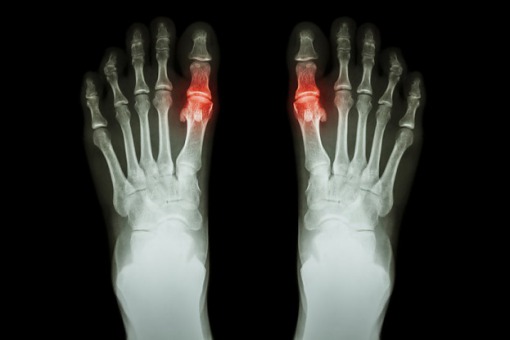

Allopurynol – będący inhibitorem oksydazy ksantynowej – pozostaje podstawowym lekiem w terapii dny moczanowej i hiperurykemii. Dotychczasowe dane kliniczne wskazują na korzystny wpływ leku na funkcję nerek oraz zmniejszenie śmiertelności wynikające z działania kardioprotekcyjnego w grupie chorych z hiperurykemią i dną moczanową.

Na łamach „Arthritis Care & Research” opublikowano wyniki (Hay i wsp.) systematycznego przeglądu piśmiennictwa i metaanalizy 4 badań obserwacyjnych, które wskazują, że w grupie chorych na dnę moczanową nie obserwowano związku pomiędzy stosowaniem allopurynolu a śmiertelnością niezależnie od przyczyny. Analizą objęto duże badania kohortowe, prowadzone w podobnym okresie dla ujednolicenia grupy.

Wyniki pracy stoją w opozycji do dotychczasowych danych wskazujących na kardioprotekcyjny i nefroprotekcyjny wpływ allopurynolu w grupie chorych na dnę moczanową. Jak zwracają uwagę autorzy pracy, jednym z powodów rozbieżności danych mogą być różnice w metodologii badań. W swojej pracy Hay i wsp. objęli metaanalizą badania obserwacyjne, w przypadku których (przeciwnie do randomizowanych kontrolowanych badań klinicznych – RCT) stosowana dawka allopurynolu mogła być niewystarczająca do uzyskania optymalnych stężeń kwasu moczowego w surowicy krwi. W RCT, w których wykazano kardioprotekcyjny efekt allopurynolu, często stosowano dawki przekraczające 600 mg/dobę, podczas gdy w codziennej praktyce klinicznej – bardzo często bez uzasadnienia – nie jest przekraczana dawka 300 mg/dobę. Istotnym problemem jest również słaby compliance w odniesieniu do stosowania leku wśród chorych z dną moczanową.

Rezultaty badania są niejednoznaczne względem oceny wpływu allopurynolu na śmiertelność z przyczyn sercowo-naczyniowych, a wyniki 2 analizowanych badań są rozbieżne. Dotychczasowe dane wskazują jednak, że w przypadku tzw. postępowania ukierunkowanego na cel i eskalacji dawki leku dla uzyskania optymalnych stężeń kwasu moczowego w surowicy możliwy jest korzystny wpływ allopurynolu na zmniejszenie śmiertelności z przyczyn sercowo-naczyniowych – konieczne są jednak dalsze badania.